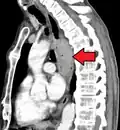

Additional testing is needed to assess how much the cancer has spread (see § Staging, below). Computed tomography (CT) of the chest, abdomen and pelvis can evaluate whether the cancer has spread to adjacent tissues or distant organs (especially liver and lymph nodes). The sensitivity of a CT scan is limited by its ability to detect masses (e.g. enlarged lymph nodes or involved organs) generally larger than 1 cm.[44][45] Positron emission tomography is also used to estimate the extent of the disease and is regarded as more precise than CT alone.[46] PET/MR as a novel modality has shown promising results in preoperative staging with fair feasibility and good correlation in comparison to PET/CT. It can enhance tissue differentiation with lowering the radiation dose to the patient.[47] Esophageal endoscopic ultrasound can provide staging information regarding the level of tumor invasion, and possible spread to regional lymph nodes.

Contrast CT scan showing an esophageal tumor (axial view)

Contrast CT scan showing an esophageal tumor (coronal view)